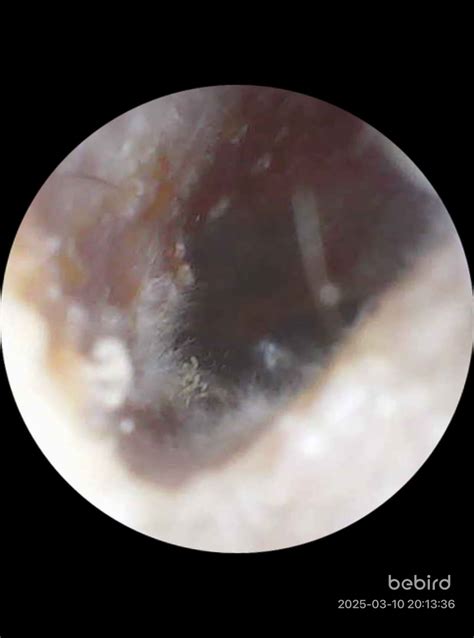

Diagnosing fungal otitis externa typically involves a physical examination of the ear. The healthcare provider will use an otoscope to inspect the ear canal and eardrum. In some cases, a sample of the discharge may be taken for laboratory analysis to confirm the presence of fungi and identify the specific type.